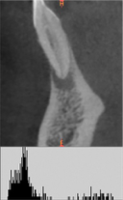

Основываясь на данных клинико-рентгенологического исследования был поставлен диагноз «хронический апикальный периодонтит 1.4» (рис. 4,а).

Пациентке была проведена операция цистэктомии с одномоментной резекцией верхушки корня зуба с последующим заполнением костной полости деминерализованной спонгиозой «Лиопласт»®.

Рис. 4. Гистограммы распределения плотности на дентальной компьютерной томографии правого сегмента верхней челюсти пациентки Т. до операции РВК зуба 1.4 с применением деминерализованной спонгиозы «Лиопласт»®(а); через 3 месяца после операции РВК (б); через 6 месяцев после операции РВК (в).

На рисунках 4(б) и 4(в) отчетливо наблюдается заполнение послеоперационного дефекта костным регенератом.

Границы новообразованной ткани не дифференцируются от окружающих костных структур.

Распределение плотности на гистограмме через 3 месяца после операции смещается к более высокому уровню (рис. 4,б).

Нарастание доли плотного компонента установлено через 3 месяца (рис. 4,б), при этом гетерогенный характер гистограммы свидетельствует о неравномерности формирования костной ткани.

Структура плотности в операционной зоне на шестом месяце наблюдения (рис. 4,в) приобретает гомогенность и находится в диапазоне, характерном для губчатого вещества кости.